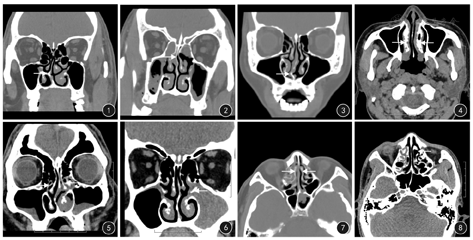

两组患者鼻腔、鼻窦结构异常典型表现见图1,图2,图3,图4,图5,图6,图7,图8。CRS组患者鼻中隔偏曲、下鼻甲肥大、泡状中鼻甲、钩突肥大等鼻腔、鼻窦异常结构发生率均高于非CRS组患者(P值均<0.05),尤以鼻中隔偏曲发生率高;而中鼻甲方向偏曲和钩突气化两种鼻腔、鼻窦部变异发生率,两组间比较差异无统计学意义(P值均>0.05)。见表1。

依据《2012昆明CRS诊断和治疗指南》中的相关诊断标准,依据鼻内镜和鼻窦CT检查,观察是否存在下列异常解剖结构:鼻中隔偏曲、泡状中鼻甲、中鼻甲方向偏曲、下鼻甲肥大、沟突肥大、钩突气化。鼻中隔偏曲位置判断:在冠状位CT片上,位于中鼻道及上方的鼻中隔偏曲为鼻中隔高位偏曲,其下方为鼻中隔低位偏曲。